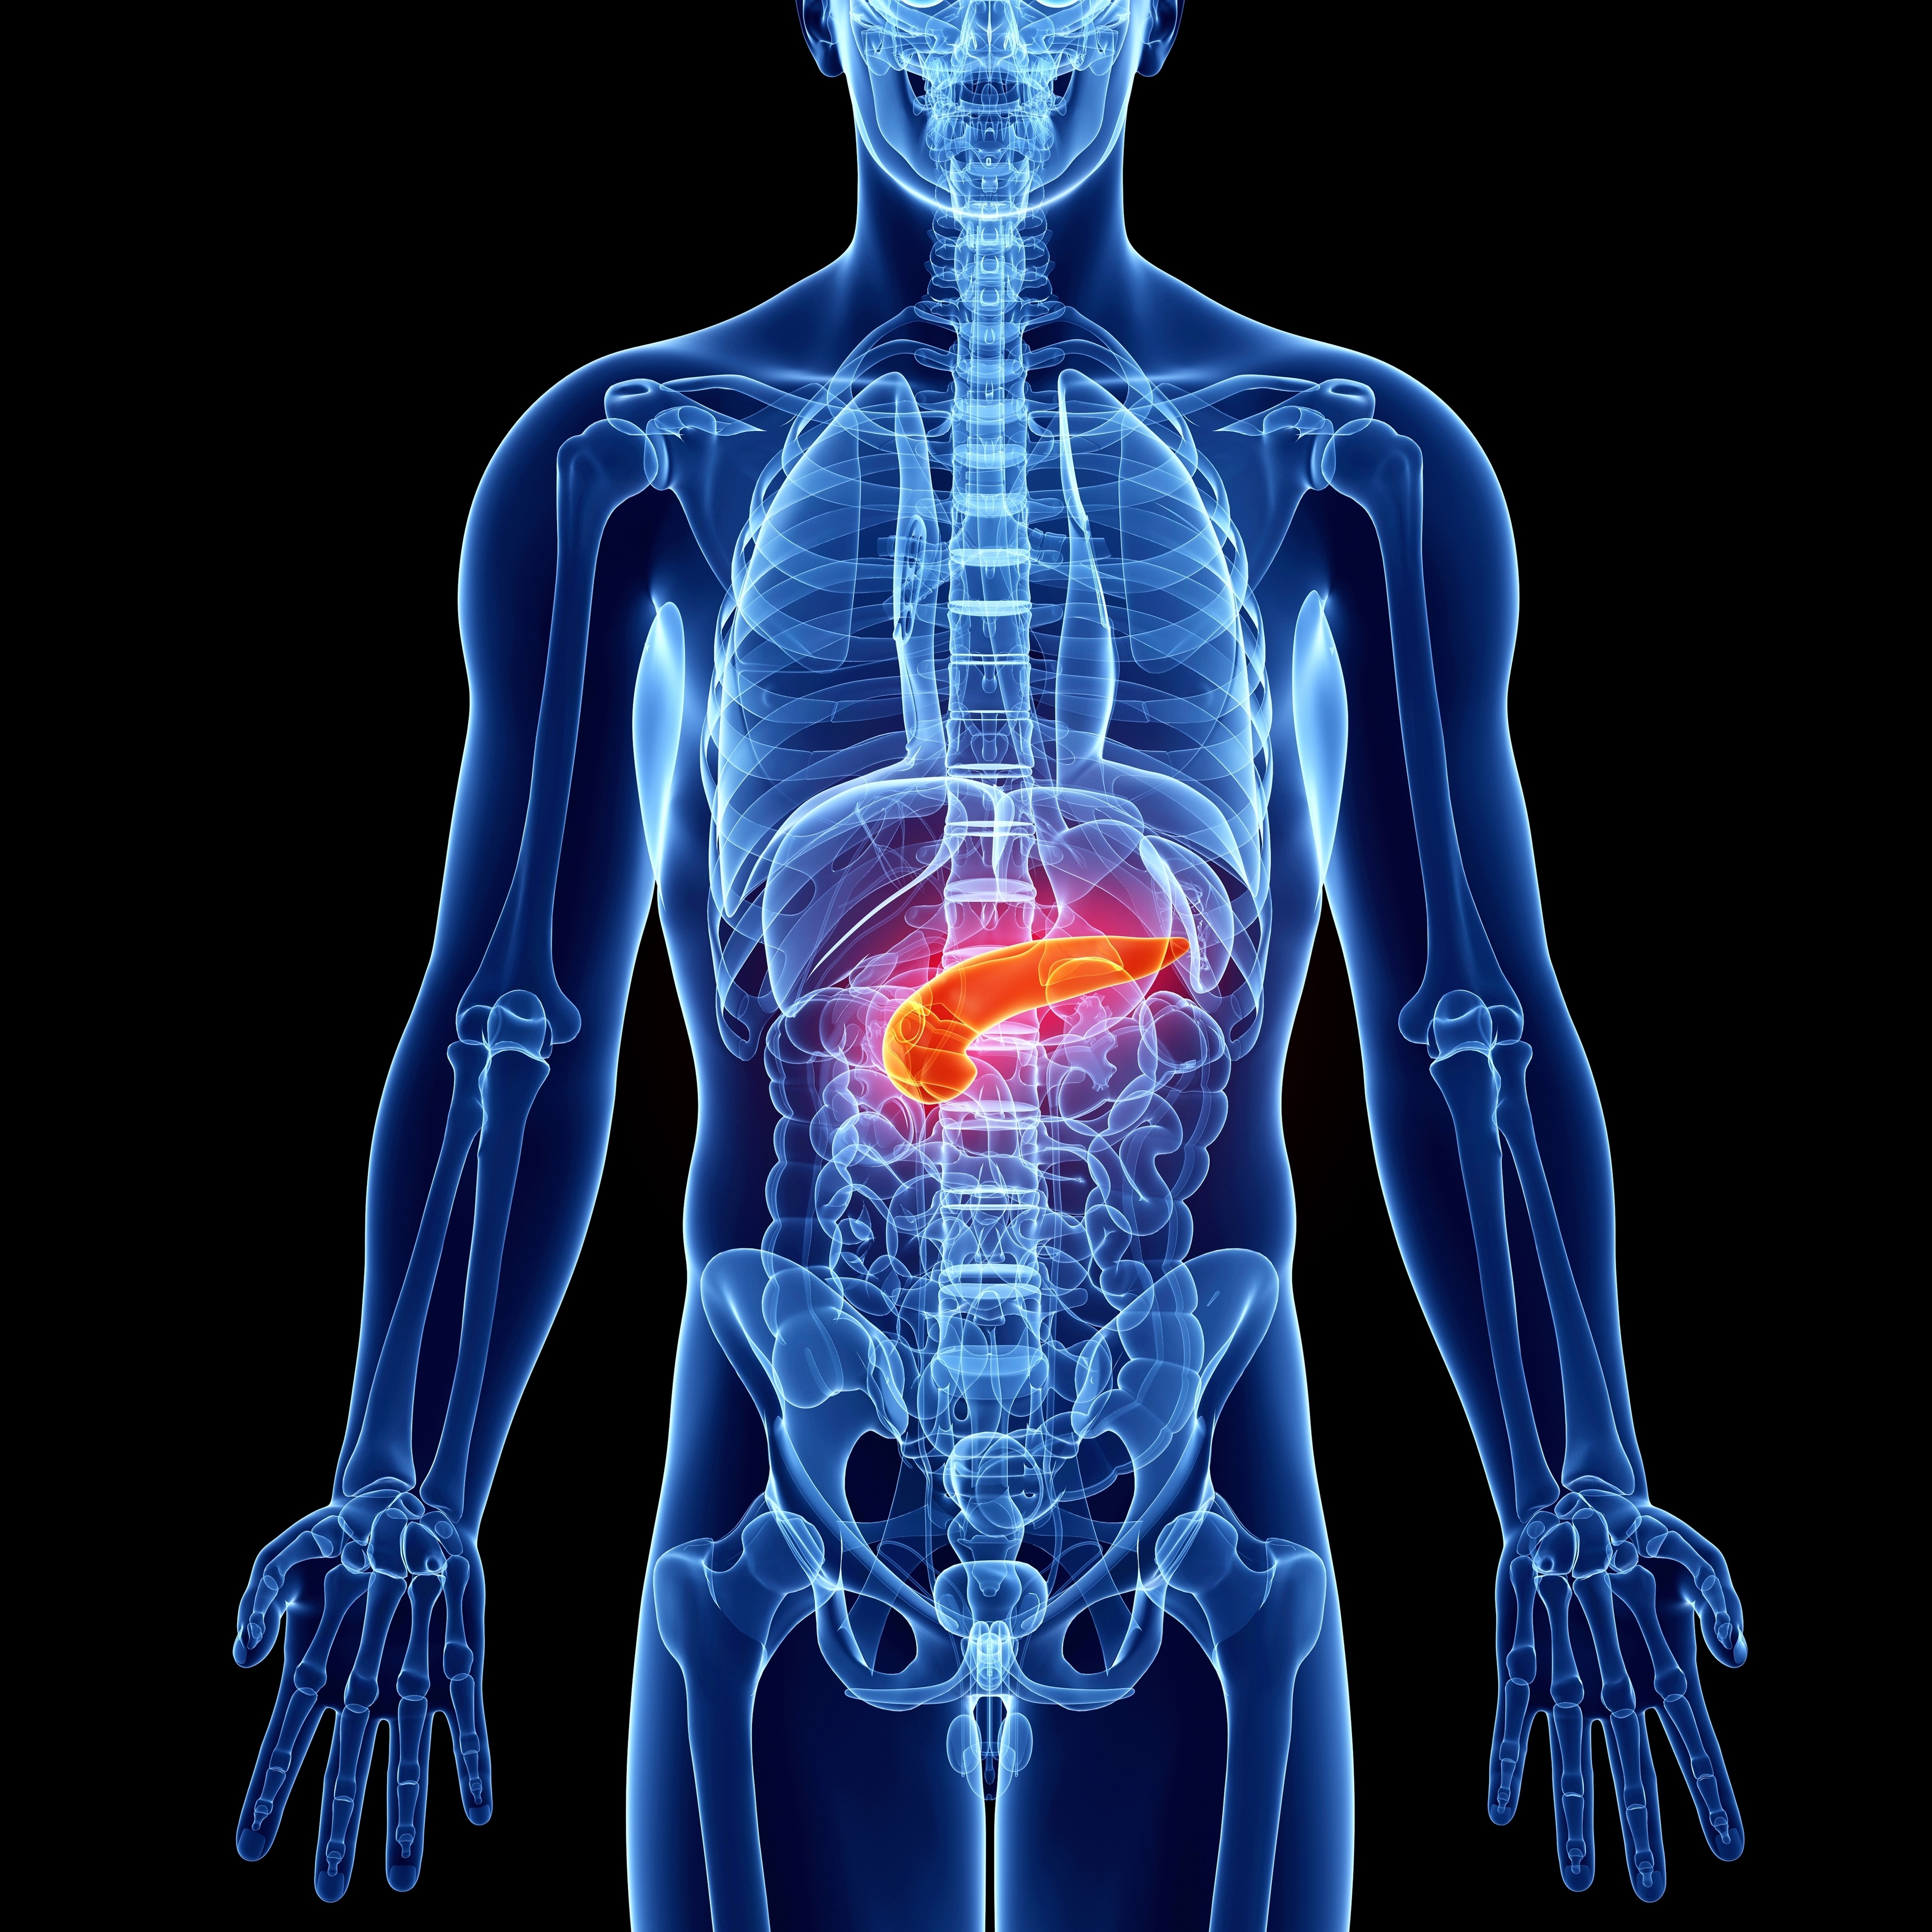

9.“The pancreas. Nobody spares a thought for their pancreas. Ever. You think organs, it’s heart, lungs, liver, and kidneys, but then your pancreas goes belly up, and you’re like.. what???”